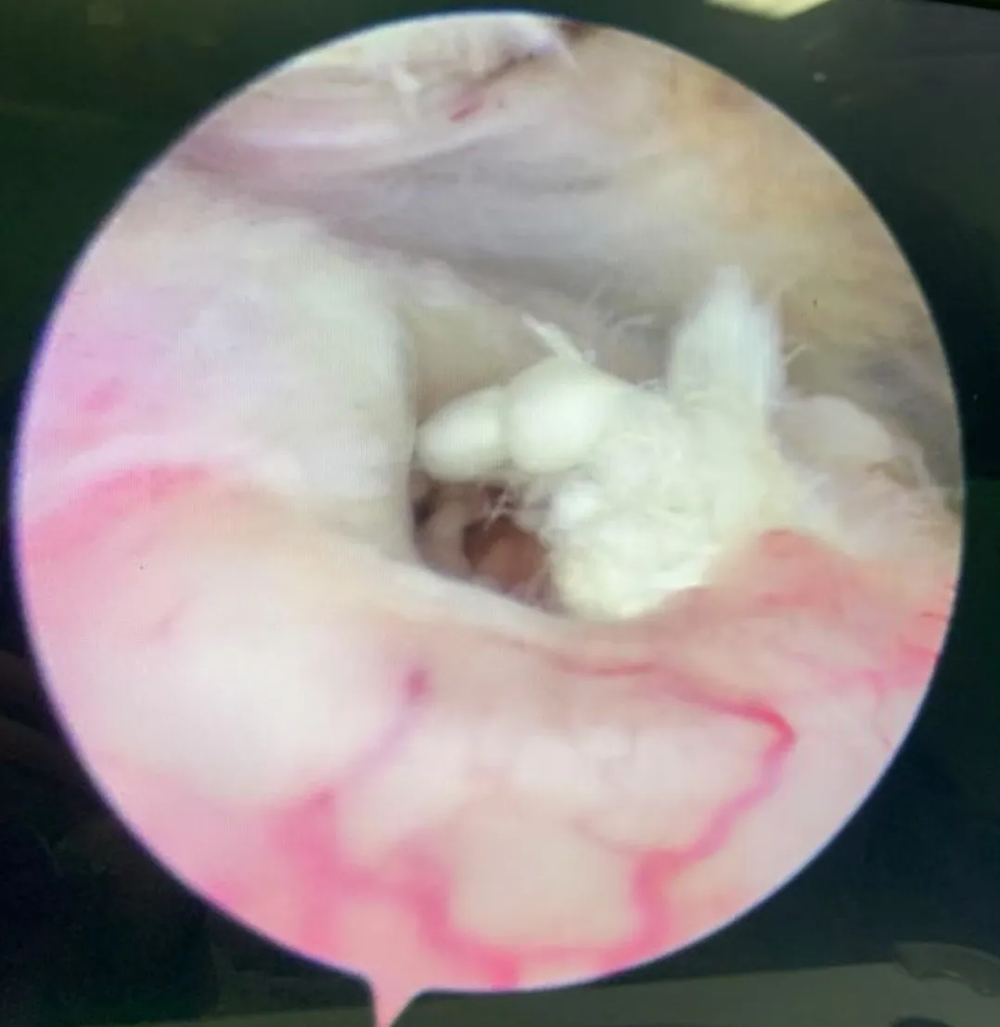

輕(qīng)微受傷,治療的首(shǒu)選往往是保(bǎo)守(shǒu)治療。這包括讓肩膀得到充分的休息,尤(yóu)其是(shì)避開那些會(huì)讓疼痛加劇的動作,必要時可以使(shǐ)用非甾體抗炎藥,它們(men)能有效控製疼痛並減輕炎症。保守治療無效時(shí),或者患者肩袖發生了(le)全層的撕裂時(shí),手術治療就顯(xiǎn)得(dé)尤為必要了,可以采取關節鏡(jìng)微創手術,切口小、出血少(shǎo)、恢複快(kuài),一般(bān)僅需3~4天即可出院,手術(shù)後經(jīng)過1-3個月的康複鍛煉,既可恢複功能。